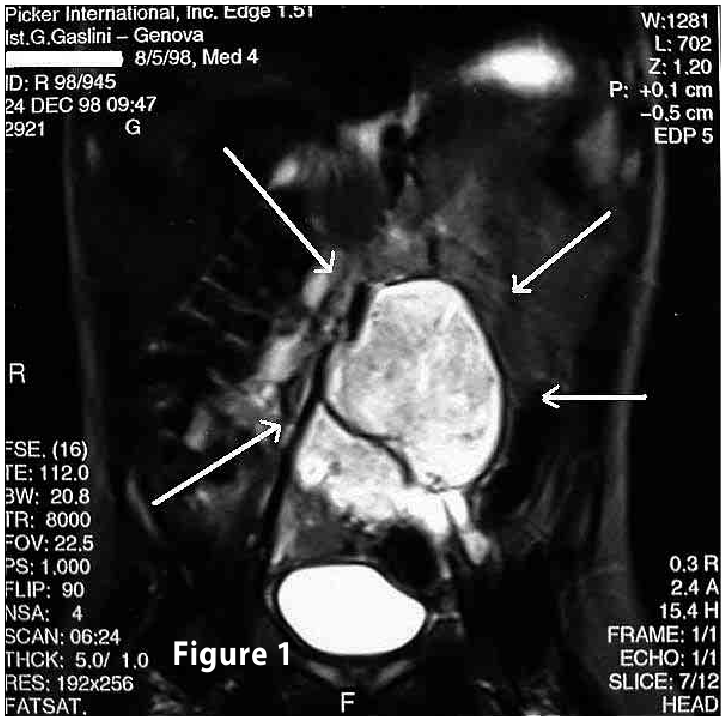

Complete objective response of neuroblastoma to biological treatment.

Figure1